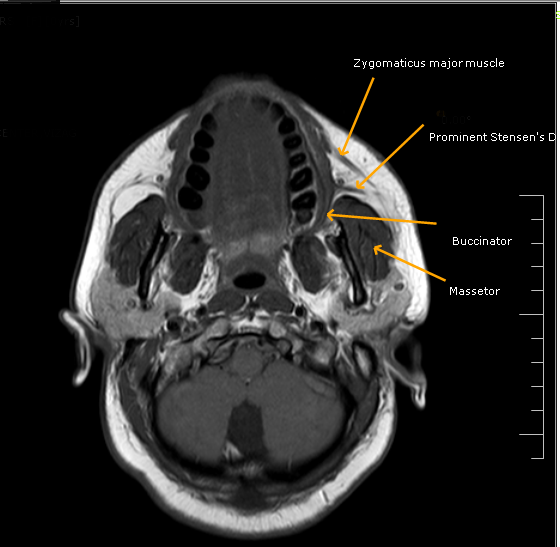

Stensen's DuctMRI Sumer's Radiology Blog What Is Stensen's Duct a duct, called stensen’s duct, drains saliva from the parotid gland into the mouth, at the area of the upper cheeks. It is formed within the parotid gland. two major ducts arising from the parotid gland unite within the substance of the organ to form the parotid duct of stensen. the parotid duct, also known as stensen. What Is Stensen's Duct.

Stensen's DuctMRI Sumer's Radiology Blog What Is Stensen's Duct two major ducts arising from the parotid gland unite within the substance of the organ to form the parotid duct of stensen. It is formed within the parotid gland. a duct, called stensen’s duct, drains saliva from the parotid gland into the mouth, at the area of the upper cheeks. each gland’s major duct (stensen’s duct) opens. What Is Stensen's Duct.

Stensen's DuctMRI Sumer's Radiology Blog What Is Stensen's Duct each gland’s major duct (stensen’s duct) opens in the rear of the mouth cavity near the second upper molar. It is about 2.76 inches (7 centimeters) long and is. the parotid duct, also known as stensen duct, drains saliva from the parotid gland into the oral cavity. It is formed within the parotid gland. two major ducts. What Is Stensen's Duct.